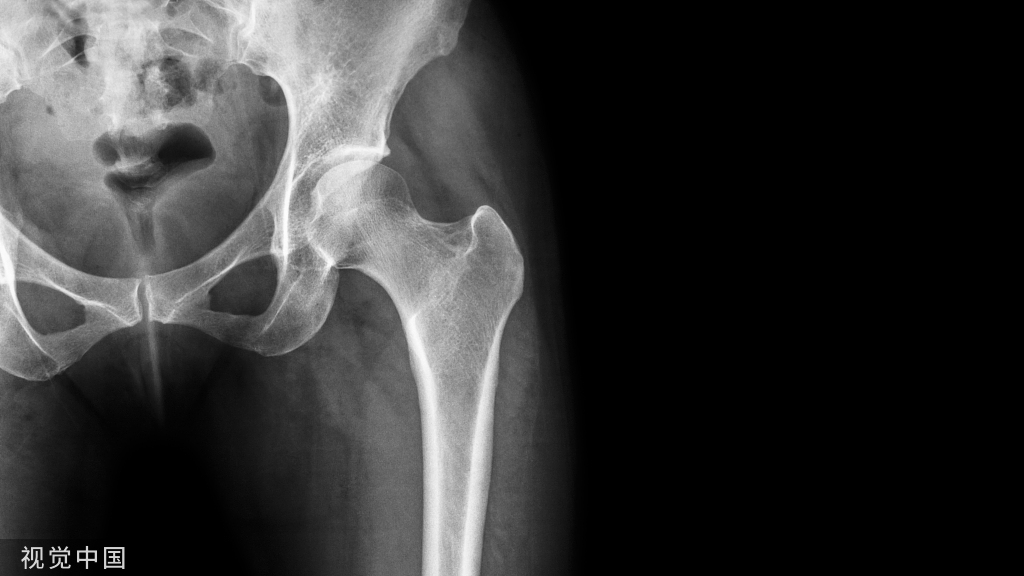

根部阻力亦可称根部骨阻力或牙根阻力,其主要根据X线片分析,阻力大小与牙位、牙根数目、牙根形态、根尖形态、根周骨组织情况有关。

牙根阻力以多根牙、根分歧过大、特长根、U形根、牙颈部倒凹大者阻力较大根尖区以近中弯曲、多向弯曲、根尖肥大者牙根阻力较大。

根周骨阻力以骨质增生和牙根有骨粘连者阻力较大,根周骨质疏松、有炎症性骨吸收者阻力较小。